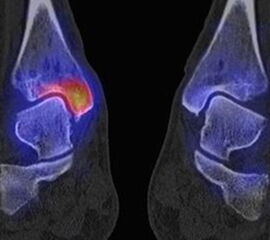

Die Abbildungen 4.2.a bis d zeigen den typischen Aspekt einer talacalcanearen Coalitio. Es besteht nur eine linksseitige, symptomatische Coalitio talocalcaneare (4.2.a und c); das 35 Tage zuvor angefertigte MRT zeigt keine auffälligen Signalveränderungen (4.2.b und d).